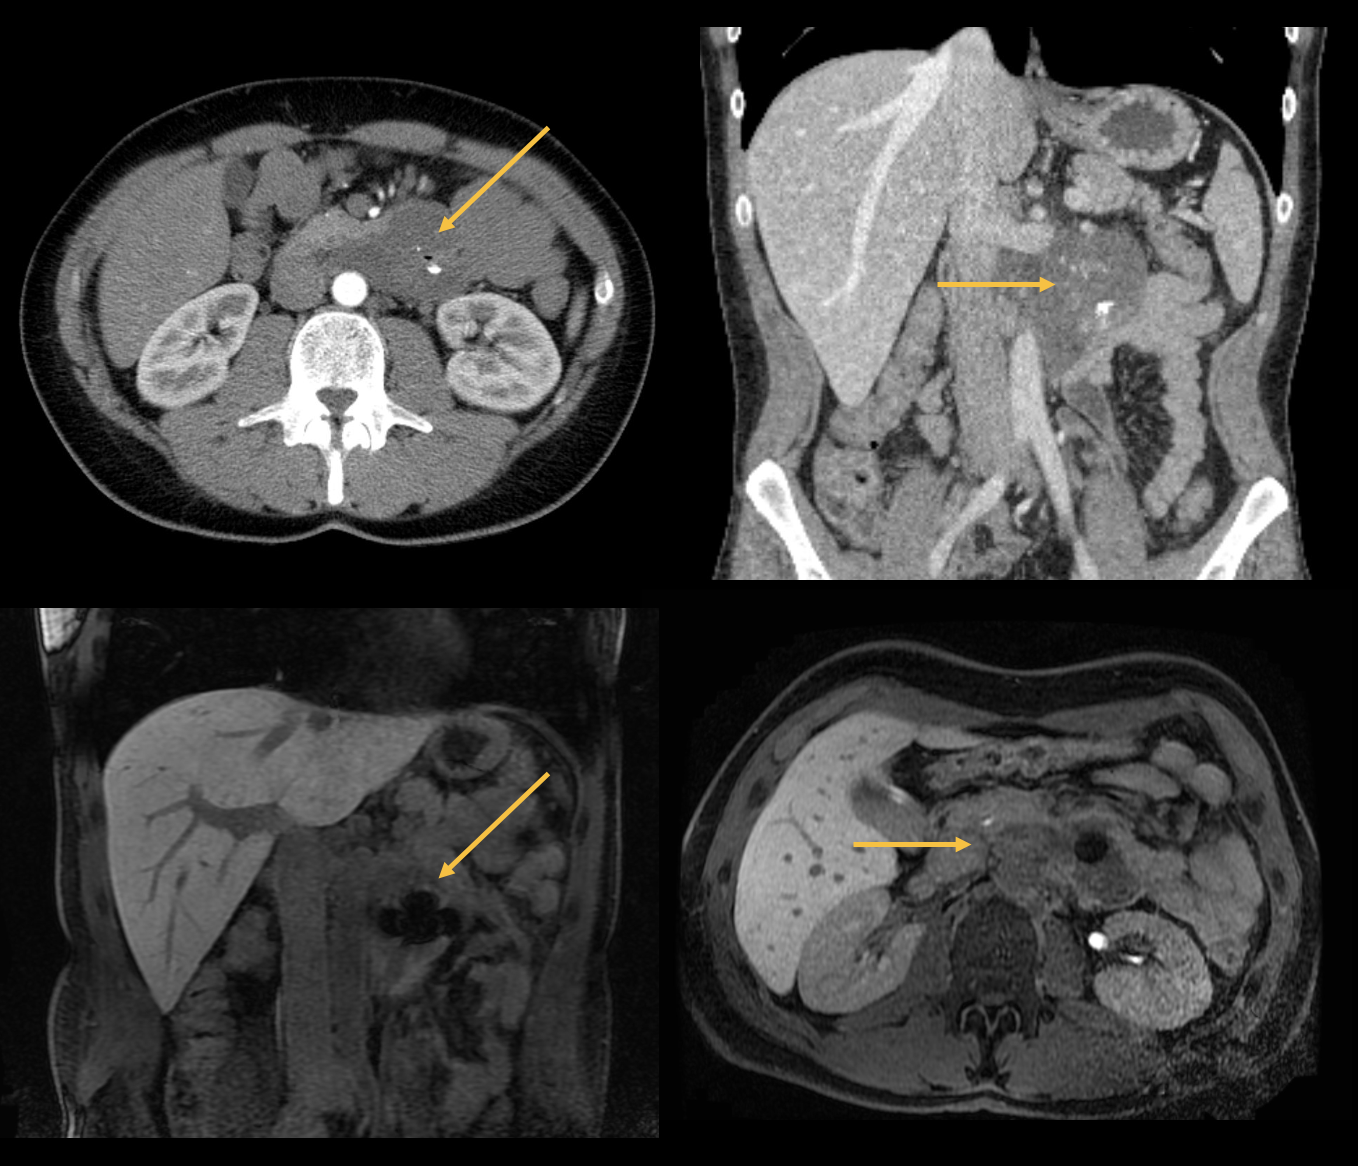

Herr H. klagte über unspezifische Beschwerden wie Völlegefühl, Bauchschmerzen, Übelkeit und Anämie. In der Bildgebung (siehe Abbildungen) zeigte sich ein gastrointestinaler Stromatumor (GIST).

GIST ist ein semimaligner Tumor des Gastrointestinaltrakts (insbesondere Magen und Dünndarm), welcher metastasieren kann, aber meist mit einer guten Prognose einhergeht. Der Tumor tritt meistens im mittleren Alter auf (40-60) und wird operativ behandelt. Bei Metastasen erfolgt eine adjuvante Immuntherapie mit einem Proteinkinaseinhibitor.

Bild 3: Axiale und koronale CT und MRT-Bilder. GIST ausgehend vom Pars horizontalis duodeni, ventral der linken Nierenvene und dem Pankreasschwanz anliegend. Zentrale Suszeptibilitätsartefakte bei Lufteinschlüssen und Verkalkungen.